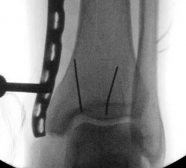

The cardinal rule of intramedullary nailing for fractures extending into the plafond is that the articular surface must be anatomically reduced and rigidly fixed before the medullary canal is reamed or the nail is inserted. Failure to do so will result in propagation of the fracture line and catastrophic displacement of the joint surface due to the hoop stresses generated by the nail.

Image

Reduction is typically achieved percutaneously using large, pointed reduction forceps. If closed reduction is inadequate, a limited open approach (anterolateral or anteromedial, depending on the fracture geometry) is utilized to directly visualize the joint surface.

Once reduced, the articular block is secured with independent 3.5 mm or 4.0 mm partially threaded cancellous lag screws. These screws must be placed strategically—typically in the anterior or posterior half of the epiphysis—to leave the central medullary canal completely unobstructed for the nail.